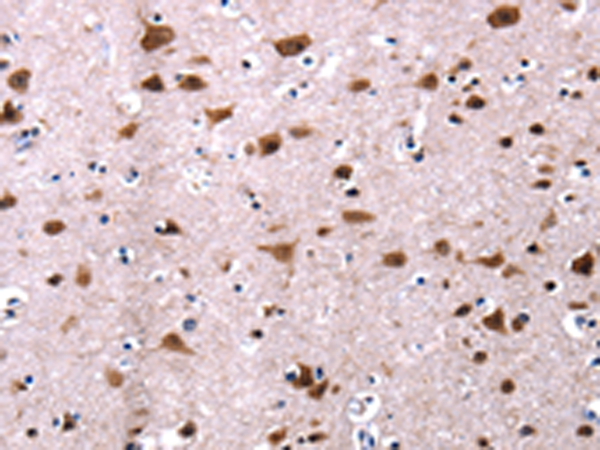

IHC positive control: |

Human brain and human cervical cancer |